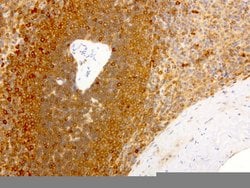

NME1 Mouse anti-Canine, Human, Rat, Clone: UMAB94, liquid, UltraMAB™

NME1 was identified because of its reduced mRNA transcript levels in highly metastatic cells. Nucleoside diphosphate kinase (NDK) exists as a hexamer composed of ′A′ (encoded by this gene) and ′B′ (encoded by NME2) isoforms. Mutations in the gene have been identified in aggressive neuroblastomas. Two transcript variants encoding different isoforms have been found for this gene. Co-transcription of this gene and the neighboring downstream gene (NME2) generates naturally-occurring transcripts (NME1-NME2), which encodes a fusion protein comprised of sequence sharing identity with each individual gene product.Specifications

| Immunocytochemistry, Immunofluorescence, Immunohistochemistry (Paraffin) | |